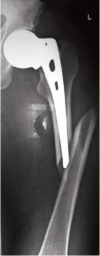

Background and objective: Intracapsular femoral neck fractures are common in the elderly population. To avoid the poor outcome of internal fixation and for early mobilization, hemiarthroplasty is performed. However, there is inadequate evidence to support the choice between unipolar or bipolar hemiarthroplasty. The aim of this study was to compare the outcome of unipolar with the bipolar prosthesis in geriatric patients.

Methods: Forty-one patients above 60 years of age and an acute displaced fracture of the femoral neck were randomly allocated to treatment by either unipolar or bipolar hemiarthroplasty, in the Department of Orthopaedics, between September 2009 and October 2012. Functional outcome was assessed and compared using Harris hip score and radiological parameters with a follow-up of one year.

Results: The two groups of patients with mean age of 67.3 in bipolar group and 75.6 in unipolar group did not differ in their pre-injury characteristics and perioperative parameters. The mean Harris hip score in bipolar and unipolar groups was 86.18±12.18 and 79.79±15.55, respectively (p=0.183); range of motion was 210.63±28.39 and 181.58±37(p=0.015) with bipolar and unipolar groups, respectively. Functional activities were better in the bipolar group. Complications like painful hip, posterior dislocation, periprosthetic fracture and acetabular erosion were encountered in unipolar prostheses.

Conclusion: The use of bipolar endoprosthesis in the management of displaced femoral neck fractures in the elderly was associated with better mean Harris hip score and incidence of complications was limited. Hence, bipolar would be a better option in elderly patients with fracture neck of femur.